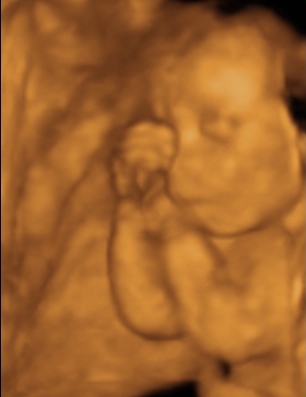

A doki szerint pufók kislány

És egy tappancs 2008.03.08 19:45